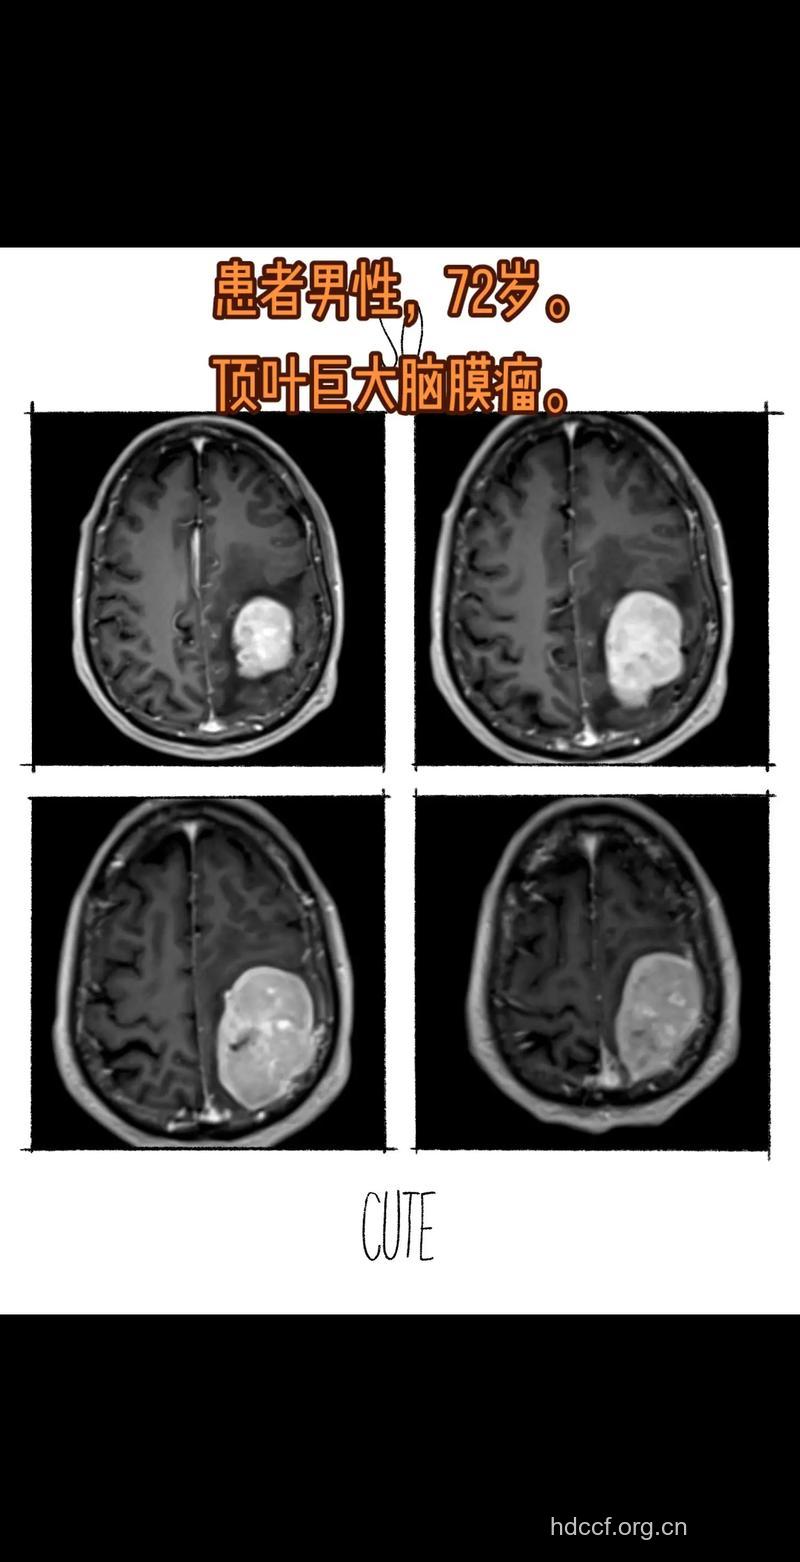

6、脑CT检查

CT对颅内肿瘤,特别是幕上肿瘤的诊断,比其它辅助诊断技术有更多的优点,是目前较为理想的检查诊断方法。